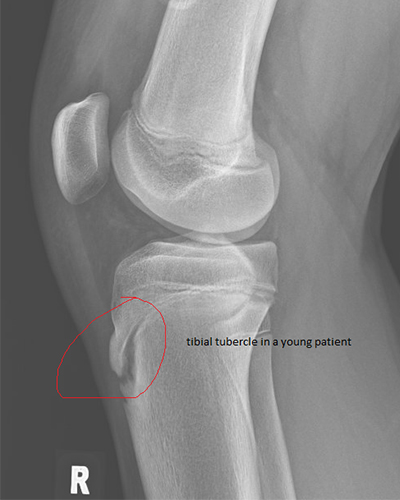

Osgood-Schlatter disease, or tibial tubercle apophysitis, is a common cause of knee pain in growing children, especially those who are active in sports. This is often due to repetitive stress or overuse, particularly in activities that involve running, jumping, or kneeling. It is caused by irritation of the area where the patellar tendon attaches to the shinbone (tibia), called the tibial tuberosity. In children, the tibial tubercle region is not fully fused down. This area is called an apophysis. Repetitive pulling on this area by the patellar tendon can cause issues. Symptoms can include pain and tenderness below the kneecap, swelling of the area, and pain during physical activity.

If the tibial tubercle region does not ever fully fuse, one can have a long term issue with a tibial tubercle ossicle. This area can continue to cause pain and discomfort down the road. Through surgical means, the ossicle can be removed and pain relief is often immediate. This video demonstrates a tibial tubercle ossicle fragment excision in a tennis athlete.